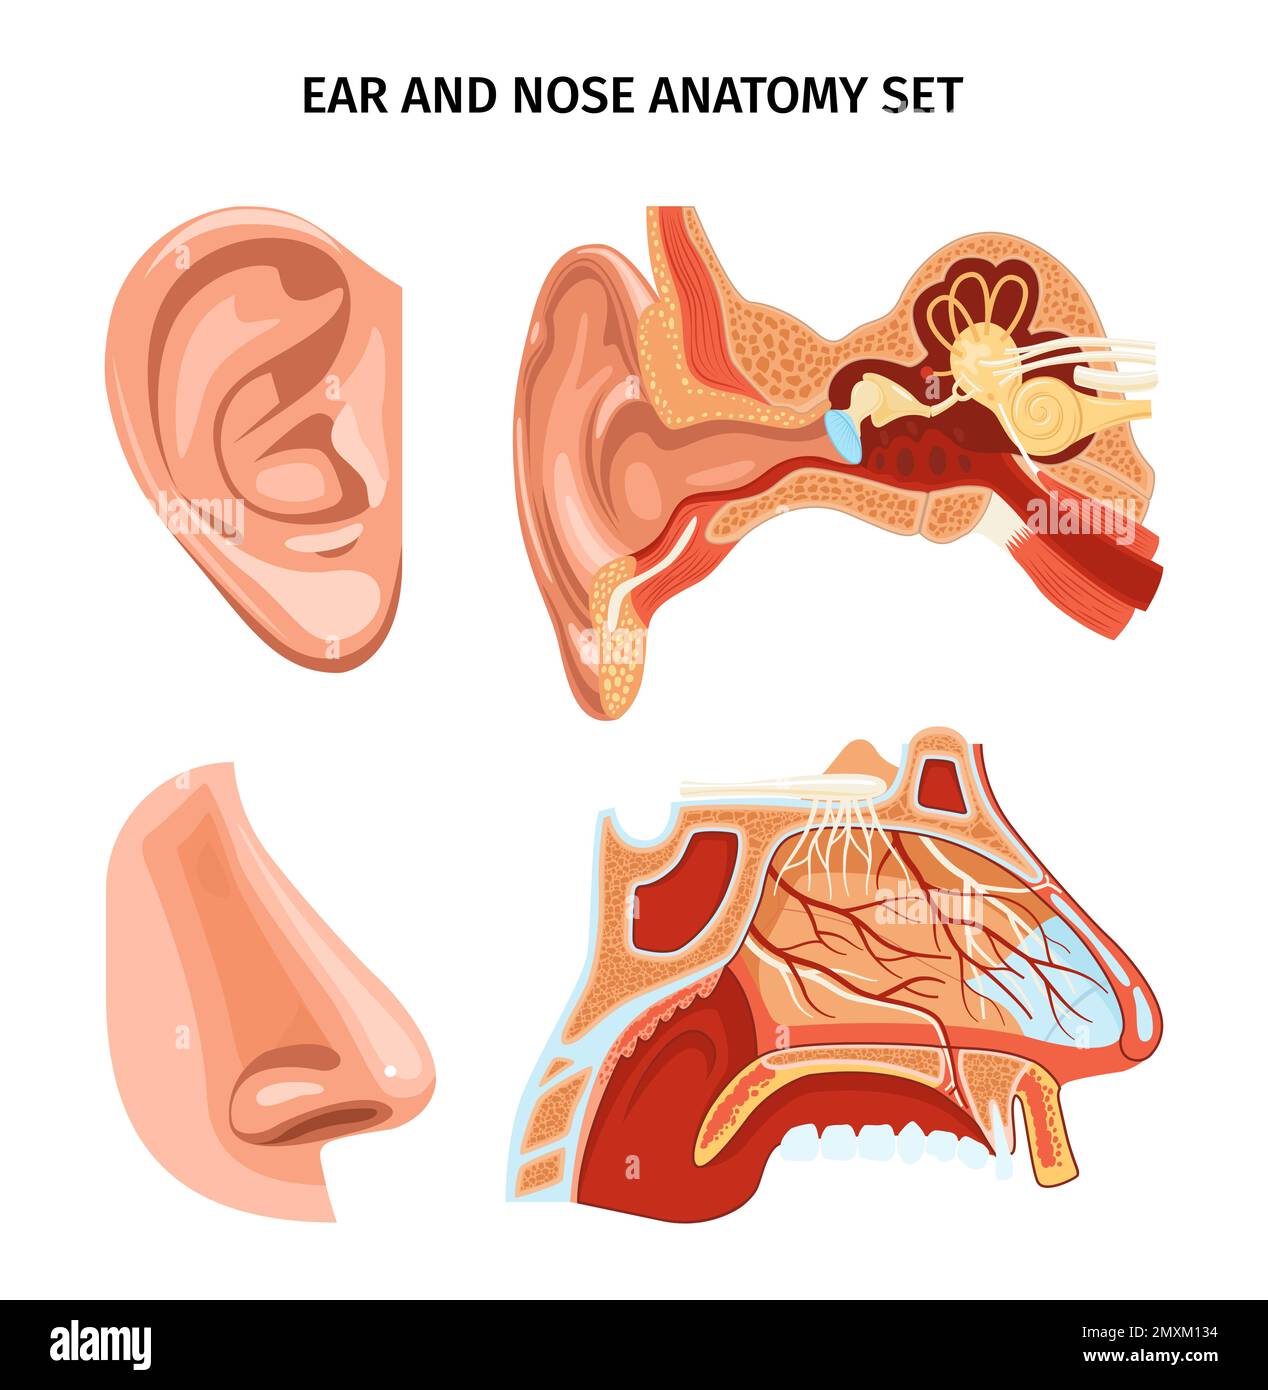

RF2MXM134–Schéma anatomique du nez et de l'oreille avec apparence et coupe transversale des organes Illustration vectorielle réaliste